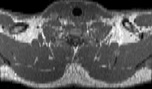

Visible Human male: Sectio transversalis 1284

NMR

Pd T1 T2